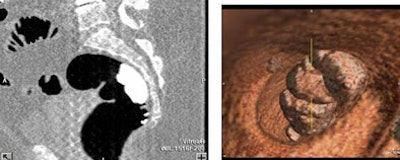

Following automated CO2 insufflation of the colon (PROTOCO2L, E-Z-EM), low-dose abdominal CT was performed on a 16-slice scanner at 50 mAs, 100 kVp, 1-mm collimation, and 0.5-mm reconstruction interval. An attending GI radiologist evaluated the images with primary 2D and 3D problem-solving software, but no computer-aided detection (CAD) or electronic cleansing software.

Compared to optical colonoscopy as the gold standard, however, VC had two false-negative adenomas larger than 10 mm. One was a flat lesion, and none were high-grade dysplasia. Three false-positives were seen in two patients with severe sigmoid diverticulosis due to small untagged fecal balls, recognized for their low density.

"We know that for those patients that had incomplete fecal tagging in the distal part of the colon, pretty much it was all because they ... identified as being constipated," Lu said. "In terms of evaluating these images, we really didn't see any beam-hardening artifact from the barium that compromised the evaluation, to our surprise," he said. Otherwise, fecal tagging was generally adequate.